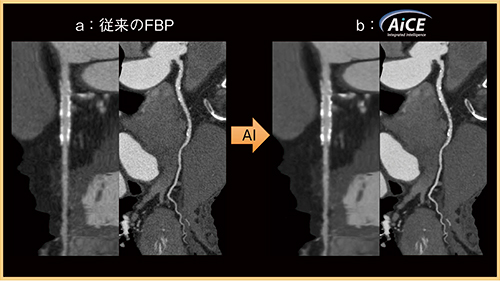

医用画像における人工知能(AI)の応用として,冠動脈CTの画質改善の例を示す(図4)。従来のFBPの画像(図4 a)と比較し,Deep Learning Reconstructionの“Advanced intelligent Clear-IQ Engine(AiCE)”を適用した画像(図4 b)では,石灰化やステント辺縁の描出が明瞭となり,脂肪や心筋のノイズが大幅に低減している。

図4 Deep Learning Reconstruction(AiCE)による画質改善